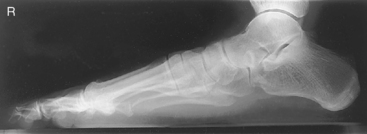

• Supine or seated with plantar surface of foot flat on IR, aligned lengthwise to portion of IR being exposed

• Extend (plantar flex) foot by sliding foot and IR distally while keeping plantar surface flat on IR. (Support with sandbags to keep foot and IR from sliding farther.)

• Supine or seated with foot centered lengthwise to portion of IR being exposed

• Oblique foot 30°–40° medially, support with 45° radiolucent angle block and sandbags to prevent slippage

• Note 1: A higher arch requires nearer 45° oblique and a low arch “flat foot” nearer 30°.

• Note 2: A 30° lateral oblique projection will demonstrate the space between 1st and 2nd metatarsals and between 1st and 2nd cuneiforms.

Lateral projection is most common for longitudinal arch (flat feet), AP demonstrates alignment of metatarsals and phalanges.